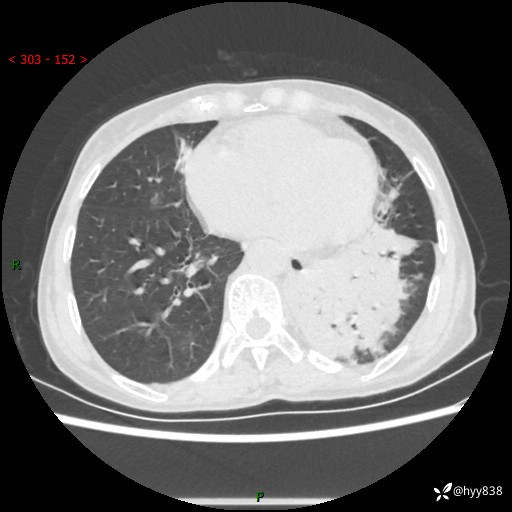

胸部CT平扫+增强